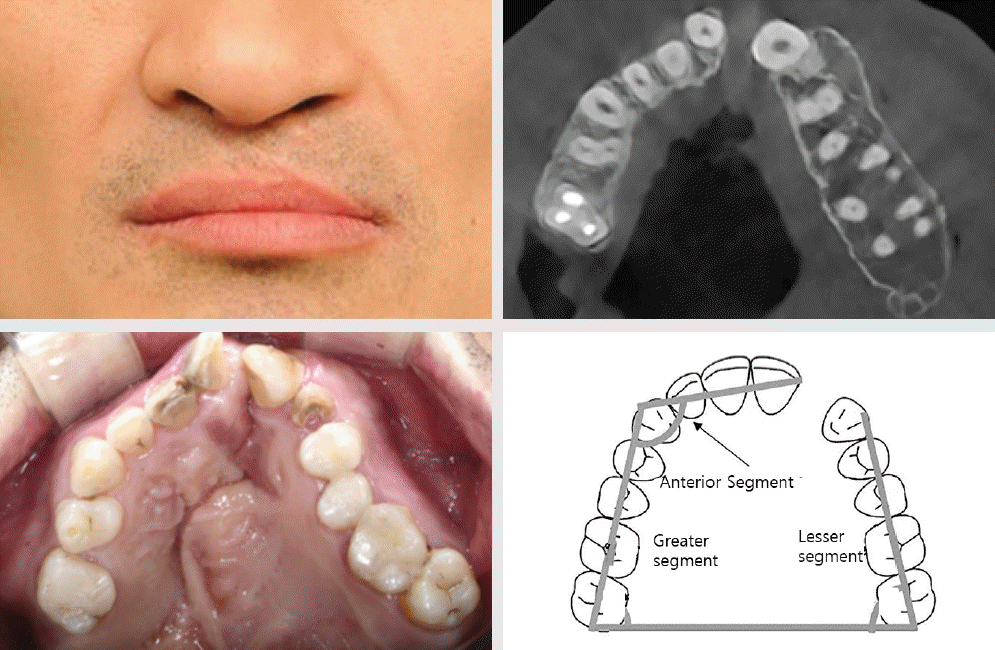

Figure 3.

Unilateral cleft lip and palate male adult patient, axial view of no previous bone graft/ orthodontic treatment history, maxillary archform compared to a diagram9.